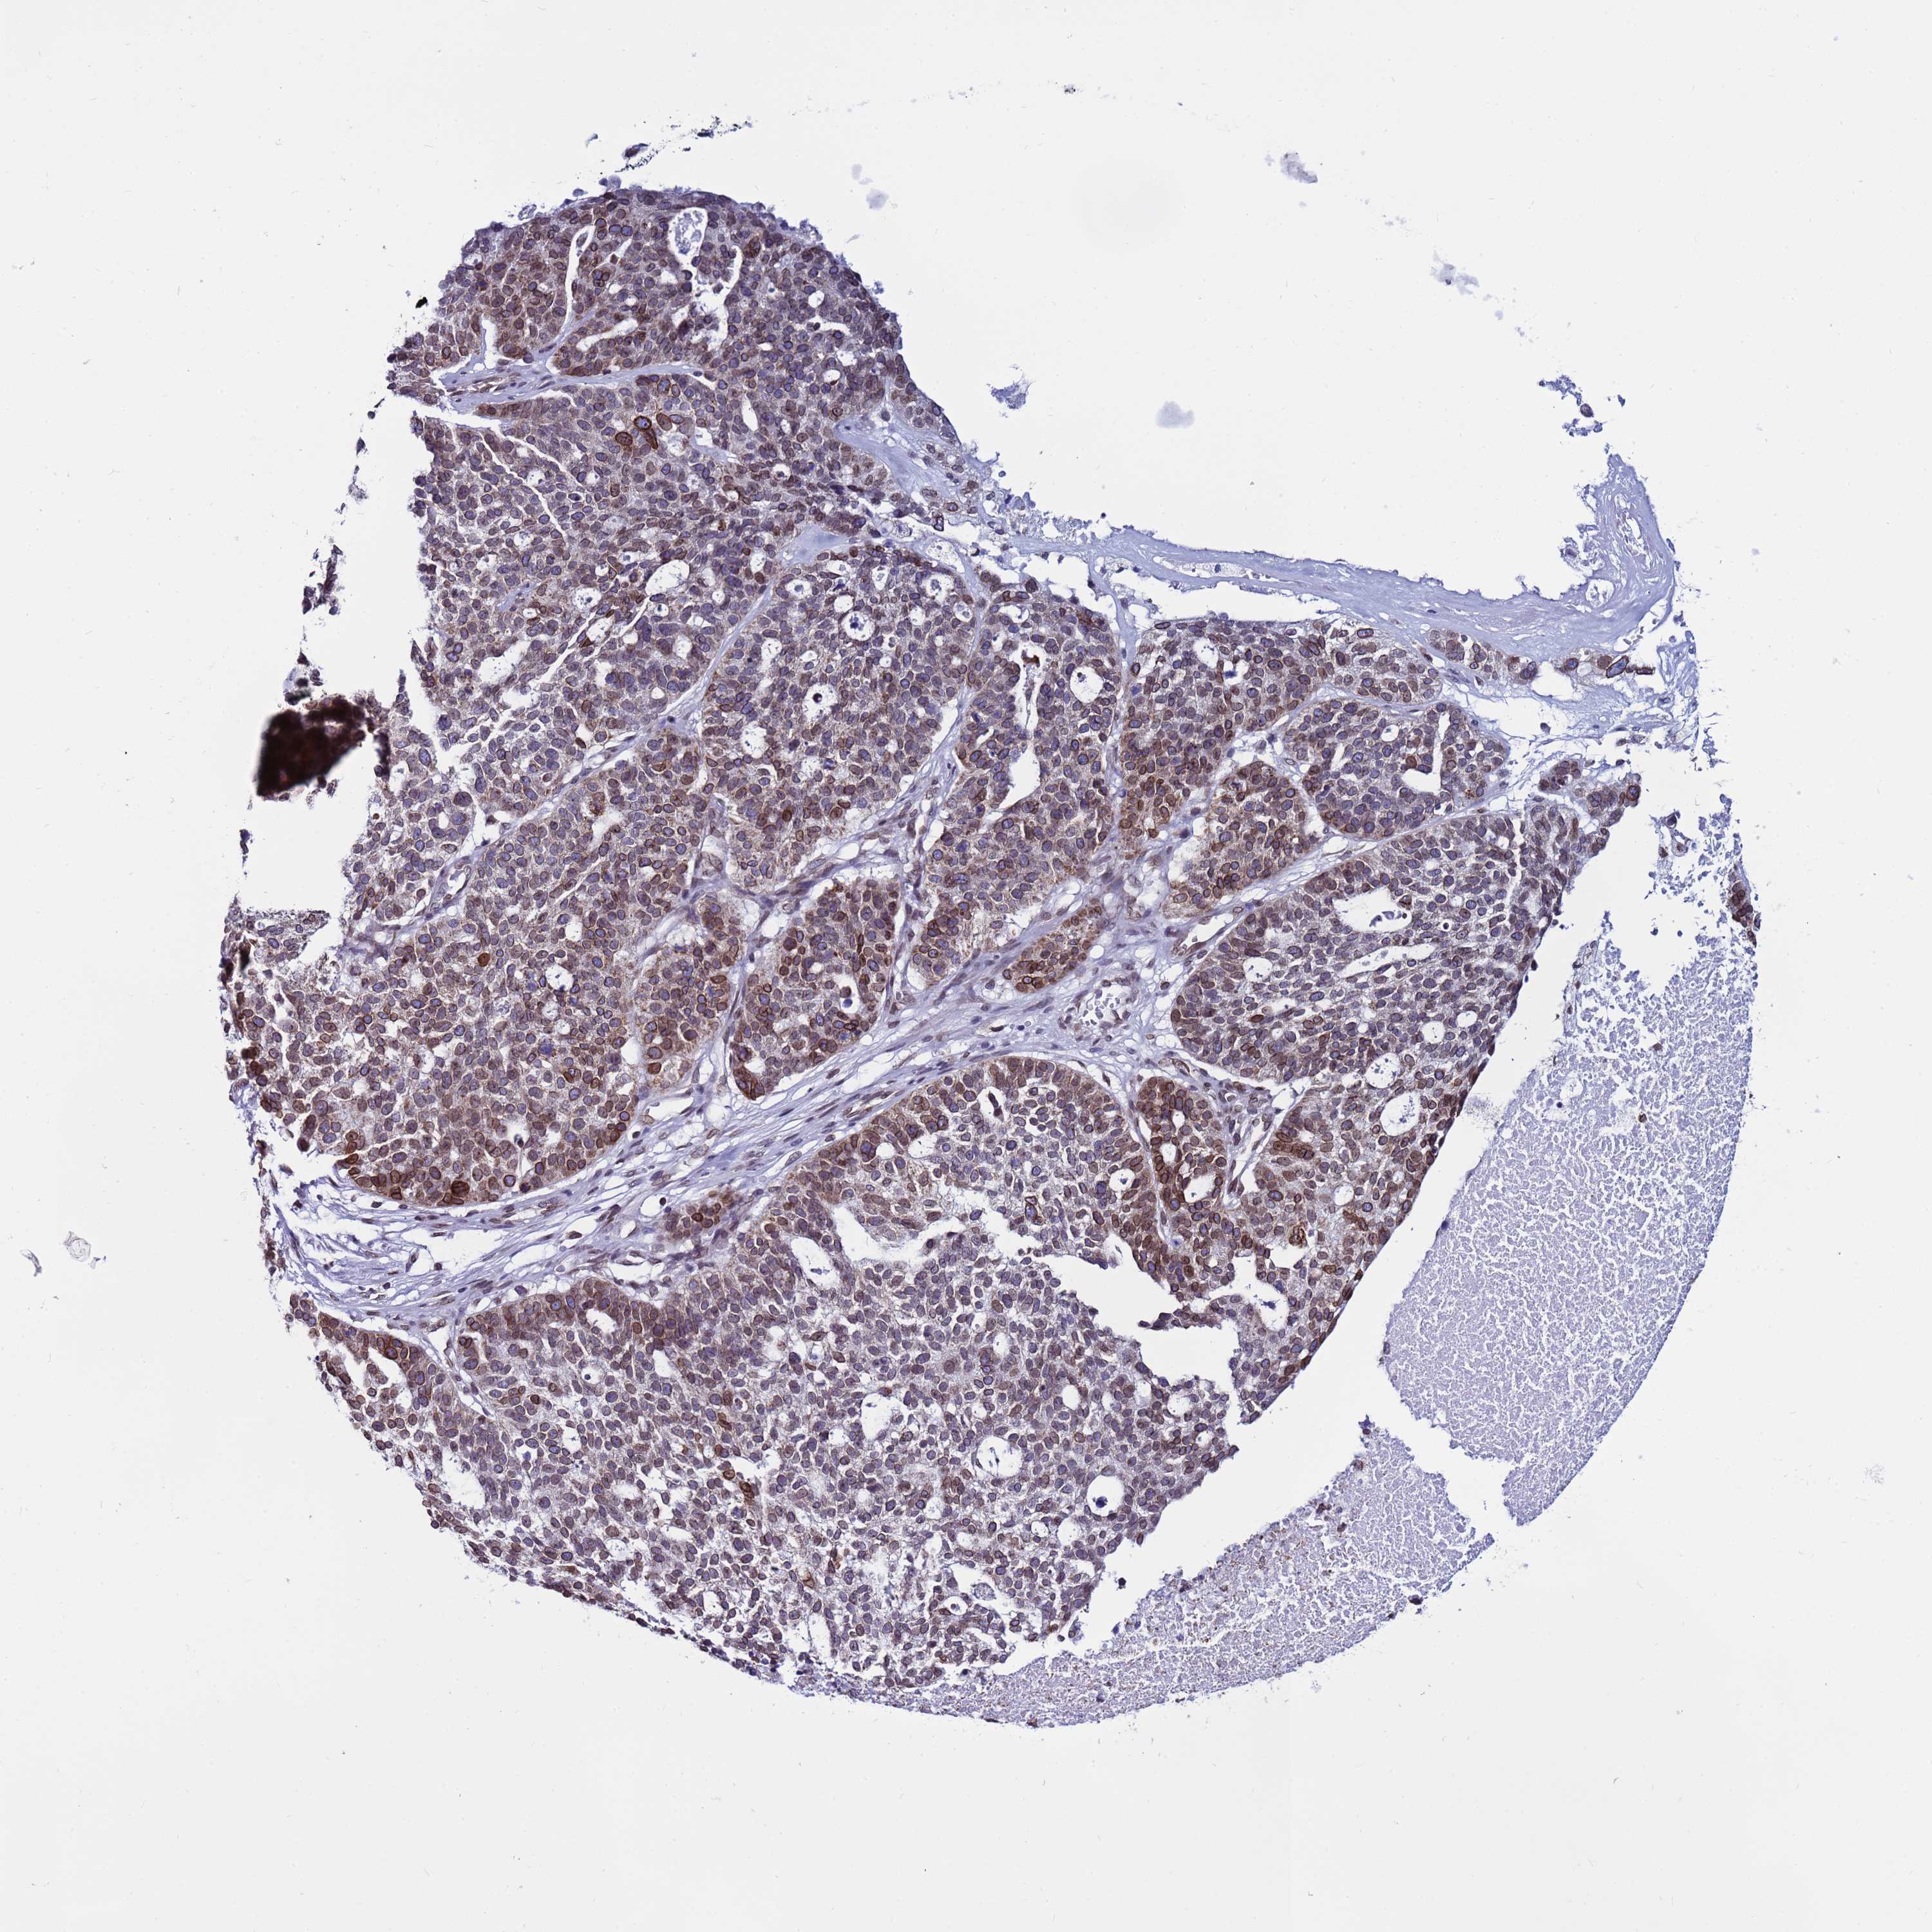

OVARIAN CANCER - Protein expressioni

A mouse-over function shows sample information and annotation data. Click on an image to view it in a full screen mode. Samples can be filtered based on level of antibody staining by selecting one or several of the following categories: high, medium, low and not detected. The assay and annotation is described here.

Note that samples used for immunohistochemistry by the Human Protein Atlas do not correspond to samples in the TCGA dataset.

Antibody stainingi

Antibody staining in the annotated cell types in the current human tissue is reported as not detected, low, medium, or high, based on conventional immunohistochemistry profiling in selected tissues. This score is based on the combination of the staining intensity and fraction of stained cells.

Each image is clickable and will lead to virtual microscopy that enables deeper exploration of all samples and also displays staining intensity scores, fraction scores and subcellular localization as well as patient and tissue information for each sample.

Antibody HPA047151

Cystadenocarcinoma, serous, NOS

Carcinoma, endometroid

Cystadenocarcinoma, mucinous, NOS

Carcinoma, NOS